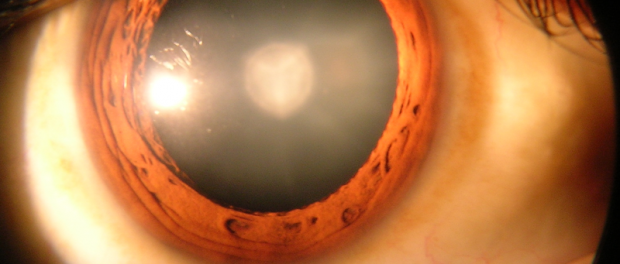

Visual acuity is our ability to see clearly. As humans our eyesight may not be as impressive as some other mammals but nevertheless it serves us sufficiently to conduct our daily activities. But eyesight problems have become commonplace in the modern world for a number of different reasons. It is lifestyle-related, due to genetics and even associated with some of the chronic diseases that have become common these days. The common causes of bad eyesight can vary. It may be a problem with the way light is bent, the amount of light that can enter the eye or a deterioration of the light-sensitive eye tissue. How Eyesight Works In order to understand how bad eyesight arises, it is first important to understand normal vision. Light rays enter the eye through the transparent cornea. The cornea bends (refracts) the light through the pupil. The refractive index of the cornea stays constant. The partially bent light now passes through the fluid in the front chamber of the eye (aqueous humor). It then passes through the lens within the eyeball. The lens can alter its shape at will to change its refractive index. This ability is known as accommodation. The light will be … Continue reading 6 Common Causes Of Bad Eyesight (Poor Vision)